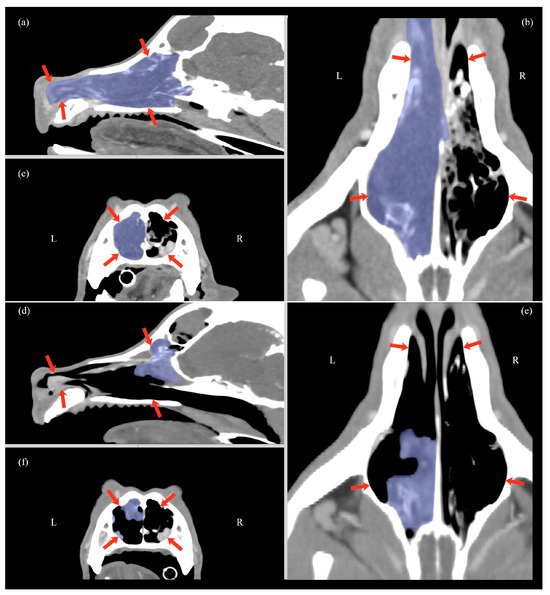

| Variable | Time | Mean | SD | min | Q1 | Q2 | Q3 | Max | p-Value w |

|---|---|---|---|---|---|---|---|---|---|

| HU | T0 | 98.2 | 6.6 | 87 | 95 | 98 | 101.5 | 110 | 0.001 |

| T1 | 60.9 | 9.4 | 50 | 52.5 | 61 | 67.5 | 78 | ||

| Attenuation reduction (%) | 37.6 | 11.1 | 11.4 | 32.4 | 38 | 46.1 | 51.8 | ||

| Volume (cm3) | T0 | 25.2 | 11.1 | 12.3 | 17.0 | 19.5 | 35.7 | 43.8 | 0.001 |

| T2 | 4.4 | 2.7 | 2.2 | 2.6 | 3.2 | 4.8 | 11.2 | ||

| Volume reduction (%) | 82.8 | 4.5 | 74.4 | 81.5 | 83.1 | 84.7 | 9.1 | ||